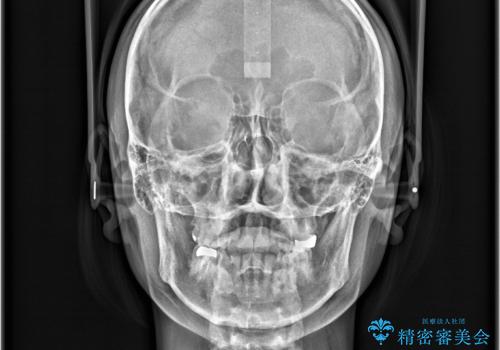

- すきっ歯と切端咬合(上下の前歯が先端で当たるかみ合わせ)を主訴にご来院された患者様です。

矯正検査を行った結果、非抜歯でインビザラインによる治療が可能と判断し、マウスピース矯正で改善を行いました。